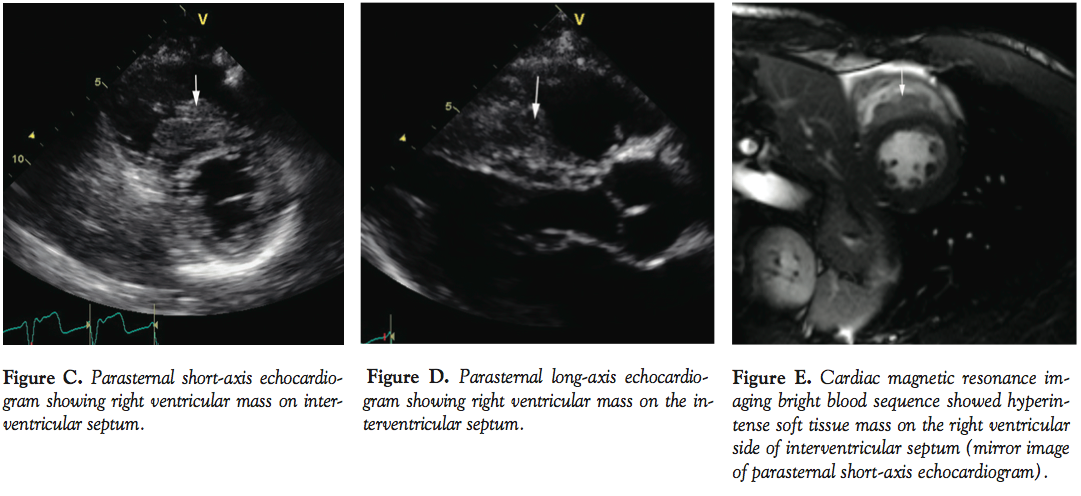

A 45-year-old African American male presented with syncope and palpitations. His electrocardiogram in the emergency department showed tachycardia (QRS duration, 114 ms) (Figure A) resistant to adenosine (max bolus dose, 24 mg). Sustained tachycardia resulted in hypotension and rhythm likely to be fascicular ventricular tachycardia was cardioverted into sinus rhythm. He subsequently had non-sustained wide complex tachycardia (Figure B) in the coronary care unit. Echocardiogram showed a mass on the right interventricular septum

(Figure C and D). He continued to have intermittent bouts of ventricular tachycardia while on intravenous amiodarone drip after amiodarone bolus. Coronary arteriography showed normal arteries. Cardiac magnetic resonance imaging bright blood sequence showed hyperintense soft tissue mass on the right ventricular side of the interventricular septum (Figure E and F). Computed tomography showed parahilar lymph node enlargement. Transbronchial fine-needle aspiration biopsy of parahilar lymph node confirmed non-caseating granulomas consistent with sarcoidosis (Figure G). The patient’s arrhythmia responded to steroid treatment.